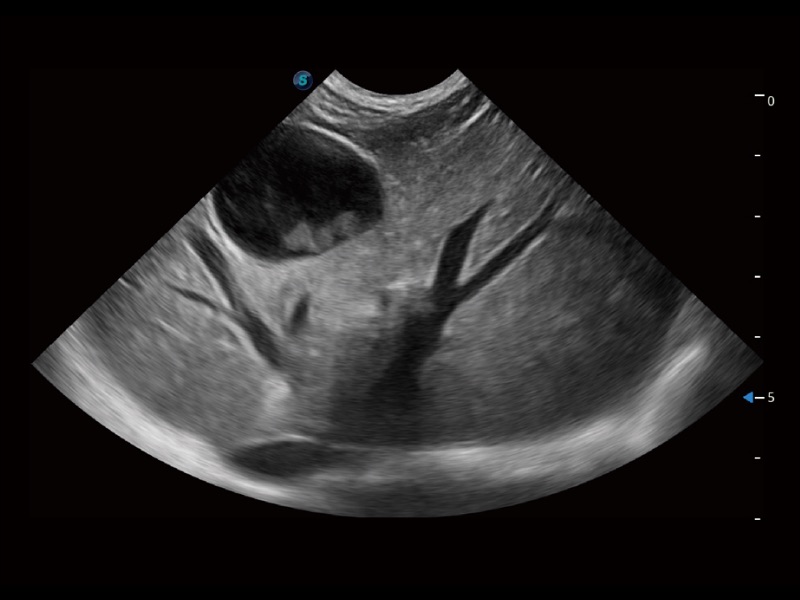

为精细结构及组织边缘提供高清晰度的图像和更大的成像视野。帮助减轻医生的用眼疲劳,快速精准获得测量的数据。